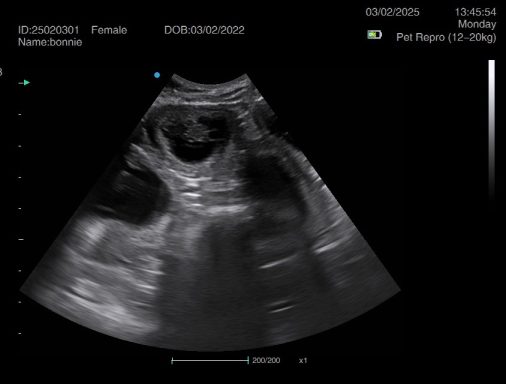

Ultrasound pregnancy scanning is a safe, non-invasive way to confirm pregnancy in dogs and cats, offering breeders and pet owners peace of mind and vital information to support responsible care. It allows us to detect gestational sacs, assess foetal development, and estimate litter size—all while ensuring the wellbeing of the animal.

Pregnancy can sometimes be detected as early as Day 18 post-mating, but scanning at this stage is not routinely recommended. Embryos are still developing and may not be clearly visible, and there is a natural risk of embryo resorption, which can lead to misleading or inconclusive results.

For the most accurate and reliable scan, we advise booking between Day 25 and Day 32, when pregnancy is more easily confirmed and foetal structures are clearer. If an early scan is performed and no pregnancy is detected, we offer a FREE complimentary re-scan after 7 days at the clinic to ensure clarity and support informed decision-making.